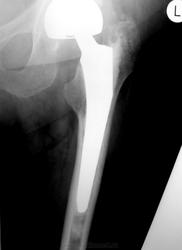

Как оценят коллеги состояние этого сустава? Возраст 77 лет, пол женский. Операция 8 мес назад.

Угол наклона чаши вертлужной впадины стремится к нулю... Расстояние от края чаши до костной основы впадины должна быть меньше 2 мм, но контур кости ровный и четкий.

Отведение вообще возможно? Протез головки бедра расположен эксцентрично, но рановато для износа полиэтилена, наверное. Нужен послеоперационный снимок для оценки динамики.

Ножка протеза беспокойства не вызывает.

По положению компонентов претензий нет. Смущает приведение в т/б суставе, но скорее всего лаборант ногу не отвел, а вообще приводяще-сгибательная контрактура у пожилых пациентов обычное дело.